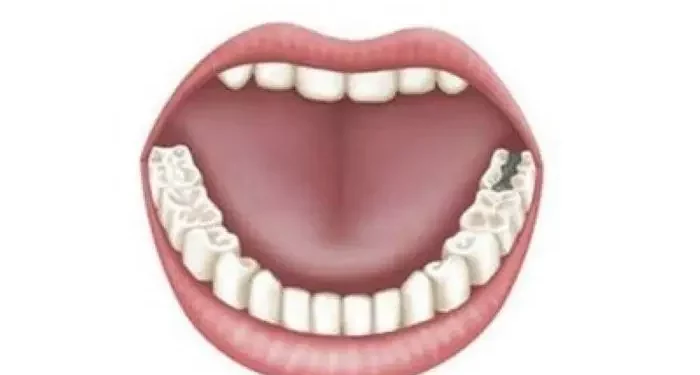

Cavities are small holes or areas of decay that form in the hard surface of teeth. They can develop in any part of the tooth, including the chewing surfaces, between teeth, or along the gum line. The primary cause of cavities is the interaction between bacteria, sugars, and the tooth surface.

Cavity Development: If demineralization continues without intervention, it can lead to the formation of cavities. Early-stage cavities may present as white spots on the enamel, while more advanced stages can result in visible holes or severe decay.